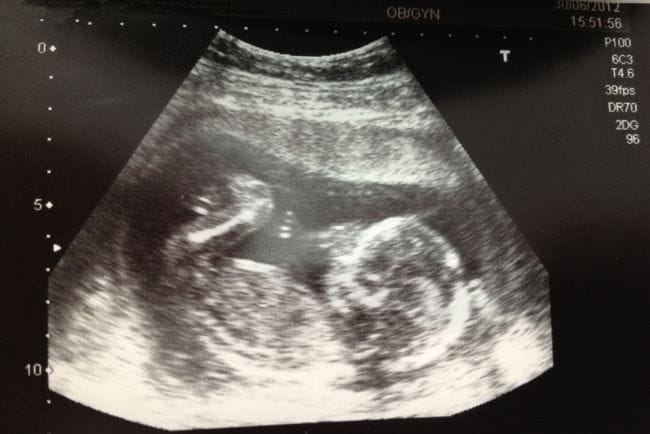

Hal-Hal yang Bisa Terlihat Melalui USG Janin 4 Bulan

USG janin 4 bulan biasanya sering dilakukan untuk melihat perkembangan janin di trimester 2. Nah, saat USG janin 4 bulan, ada beberapa hal yang umumnya bisa diketahui, yaitu:

1. Perkembangan fisik janin

Pada usia kehamilan 4 bulan, bentuk tubuh janin memang sudah terlihat makin jelas, Bun. Melalui USG janin 4 bulan, dokter bisa melihat kepala, wajah, tulang punggung, tangan, dan kaki dengan lebih jelas. Bahkan, jari-jari tangan dan kaki juga bisa terlihat.

Selain melihat bagaimana perkembangan janin, dokter akan mengukur panjang janin dan diameter kepala untuk memastikan pertumbuhan janin sesuai usia kehamilan.

Tidak hanya itu, gerakan janin seperti menendang ringan atau menggenggam tangan, juga mulai bisa terlihat di layar USG. Meski begitu, ibu hamil biasanya belum merasakannya secara langsung.